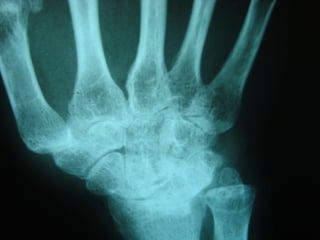

Achados radiográficosAchados radiográficos

 Osteopenia peri-articularOsteopenia peri-articular

 Diminuição do espaço articularDiminuição do espaço articular

 Presença de cisto e erosõesPresença de cisto e erosões

 Edema de partes molesEdema de partes moles

 Presença de deformidadesPresença de deformidades

1- osteopenia 2-erosões 3-sub-luxação